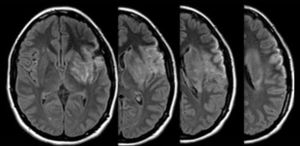

Caso clínicoMujer de 28 años, oriunda de Brasil, diestra. Sin antecedentes de FRCV clásicos, utilizó parches de etinilestradiol como anticonceptivo en el año previo a la consulta, sin uso de otras medicaciones ni consumo de tóxicos. Ingresó al departamento de emergencias por afasia mixta, hemianopsia homónima derecha y paresia facio-braquio-crural derecha de instalación súbita. En el examen se constató una escala de NIHSS de 16 puntos. Se realizó tomografía axial computarizada (TAC) de encéfalo, donde se evidenció leve borramiento del ribete insular y ganglios basales izquierdos, junto a hiperdensidad espontánea en M1 izquierda. Se comenzó trombólisis intravenosa a las 2 h y media de iniciados los síntomas, la cual finalizó sin complicaciones. La TAC de control a las 24 h y la resonancia magnética (RM) (realizada al quinto día del evento) confirmaron el infarto en el territorio de la arteria cerebral media izquierda, con compromiso de ganglios basales, corteza fronto-insular y corteza temporal lateral. En la angio-RM se evidenció amputación a nivel de M1 izquierda y circulación colateral leptomeníngea (figs. 1 y 2).